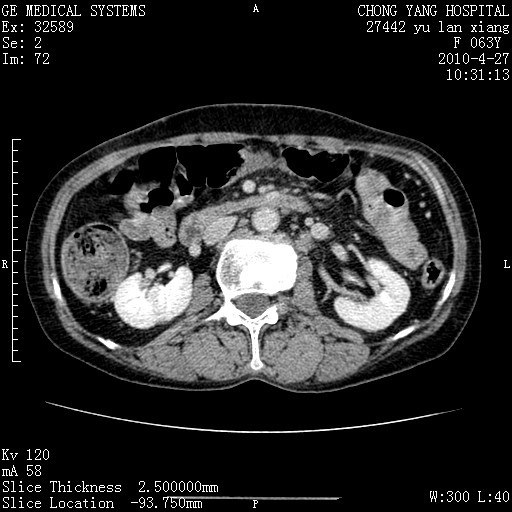

标题: CT26066:F63Y 上腹正中压痛半月,CA199:7400u/ml,MR示胰腺炎伴 [打印本页]

胰腺癌侵犯腹腔动脉干-分支、胃壁、左侧膈肌伴胰周及腹膜后淋巴结转移、胆囊切除术后。

胰腺癌侵犯腹腔动脉干-分支、胃壁、左侧膈肌伴胰周及腹膜后淋巴结转移、胆囊未显影。